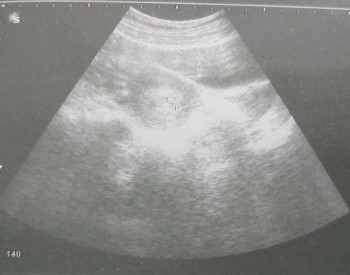

Gebelik Kesesi Hamileligin Kacinci Haftasinda Gorulur

Gebelik Kesesi Ne Zaman Gorulur